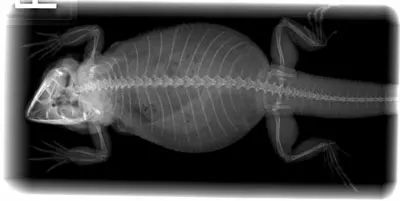

Imaging. The whole-body radiograph was unremarkable.

Figure 2: The radiograph of the bearded dragon did not help determine the cause of the cloacal prolapse